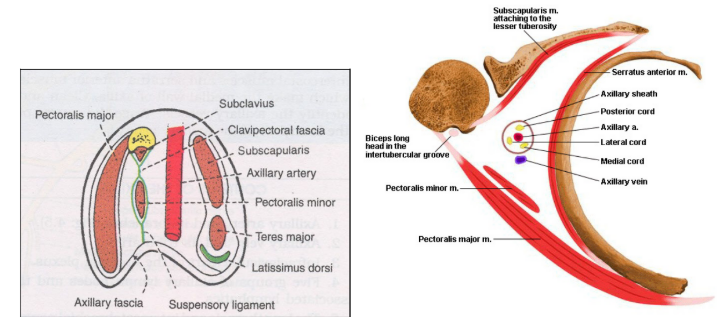

Axilla

Has apex, base and 4 walls

Apex

In front clavicle

Behind superior border of scapula

Medially outer border of 1st rib

Anterior wall

Pectoralis major and minor, clavipectoral fascia and subclavius

Posterior wall

Subscapularis, teres major and latissimus dorsi

Medial wall

Upper 4 ribs with their intercostal muscles

Lateral wall

Formed by upper part of shaft of humerus and coracobrachialis

Contents of axilla

Axillary artery

Axillary vein

Infra-clavicular part of brachial plexus

Axillary lymph nodes (anterior, posterior, lateral, central, apical)

Long thoracic nerve

Intercostobrachial nerve

Axillary pad of fat

Brachial plexus

Formed from ventral rami C5 to T1

Branches from cord

Lateral cord

Lateral pectoral nerve

Lateral root of median nerve

Musculocutaneous nerve

Medial cord

Medial root of median nerve

Medial cutaneous nerve of arm

Medial cutaneous nerve of forearm

Medial pectoral nerve

Ulna nerve

Posterior cord

Upper subscapular

Lower subscapular

Thoracodorsal nerve

Radial nerve

Axillary nerve